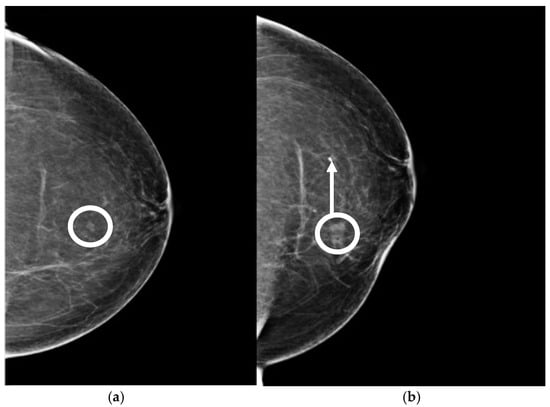

Figure 15. Left: prebiopsy image showing a suspicious distortion (circle). Right: The biopsy cavity and clip marker are both centered at the lesion.

Figure 16. (a) Pre-biopsy mammogram revealing a mass in the inner quadrant of the left breast. (b) Post-biopsy mammograms revealing a cavity centered at the lesion (circle) but lateral displacement of the clip marker (arrow).